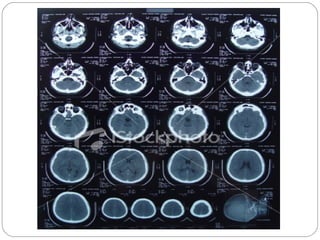

Computed Tomography (CT)

1. Also called CAT scanning or “CT”

2. X-Ray beam moves 360 around the patient

3. Consecutive x-ray “slices” around the patient

4. Computer can recreate 3D image of the body or

Image “slices” reconstructed by computation

5. Best for evaluating bone and soft tissue tumors,

fractures, intra-articular abnormalities, and

bone mineral analysis

Computed Tomography

6. The image formed is related to the subjects

density

7. Image display on computer or multiple films

8. New technology is multislice helical scanner

CT (by Picker)